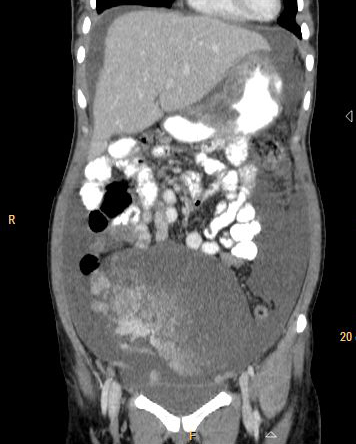

Stage 3: peritoneal implants outside pelvis or inguinal or retroperitoneal lymphadenopathy. Implants can be omentum, liver, parietal peritoneum. Peritoneal dissemination is characterised by peritoneal thickening, nodular lesion, stellate nodules located within mesentery or omentum. Stage 3a, b, c differ in size of lesion- 3a-tumour grossly limited to pelvis and gross ascites; 3b-peritoneal implant 2cms or less; 3c-implant size is more than 2cms . Retroperitoneal and inguinal adenopathy qualifies as stage 3c (Figures 6, 7 & 8).

Figure 6: 52y/F - Omental deposits (arrow) stage 3 disease.

Figure 7: 24y/F- Mucinous carcinoma of ovary, thick septations infiltrating uterus, rectum and pelvic side wall and peritoneal deposit (arrow).

Figure 8: Two different cases of carcinoma of ovary with omental and peritoneal thickening stage 3.